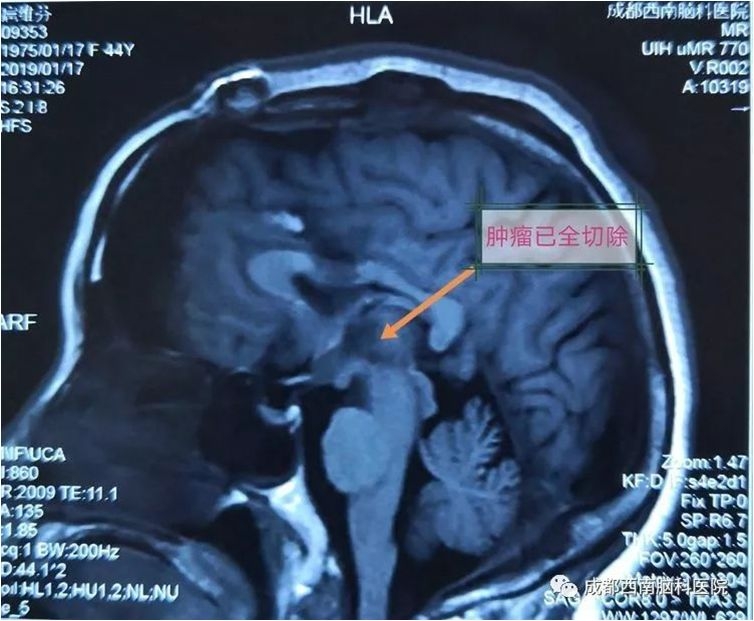

中脑海绵状血管瘤手术

术后